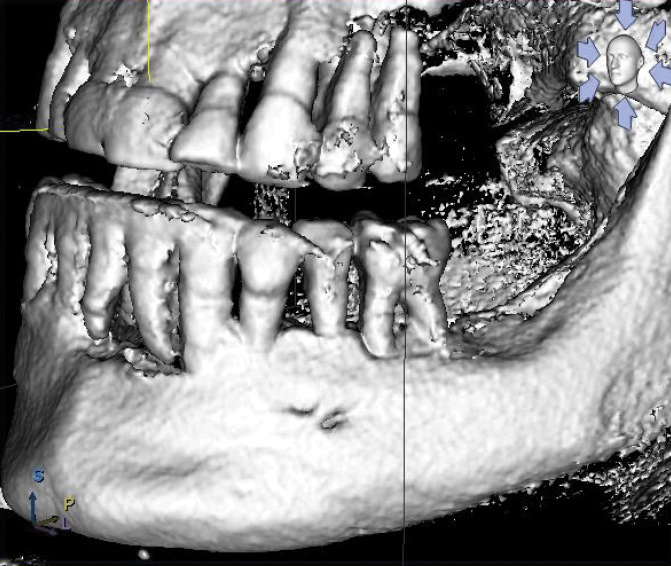

Fig 11. Accessory mental foramina (arrows) encountered during mandibular All-on-4–style dental implant surgery.

Figure 11

Fig 12. CBCT imaging of accessory mental foramina from Figure 11.

Figure 12

Fig 13. Mental foramen used to determine the posterior extent of tilted dental implant placement in a mandibular All-on-4–style dental implant surgery.

Figure 13

Accessory Mental Foramina

The prevalence of accessory mental foramina is well documented in dental literature with findings from 2.7% to 13% (Figure 11).30-32 Accessory mental foramina pose a particular obstacle for All-on-4–style treatment because the mental foramen is the landmark used to determine the posterior limits of tilted implant placement (Figure 12).9 The presence of accessory mental foramina often requires more mesial placement of dental implants, thus limiting the anterior-posterior spread of the All-on-4–style prosthesis. Furthermore, in cases in which accessory mental foramina are located superior to the main mental foramen,30 the amount of bone reduction may be compromised, increasing the risk for prosthetic fracture.25 Presurgical cone-beam computed tomography (CBCT) scans and radiographs for proposed All-on-4–style surgeries should be scrutinized for accessory mental foramina (Figure 13). Notably, dental literature has shown that even with careful evaluation of CBCT scans, it is not possible to identify 100% of accessory mental foramina cases.31 As such, care should be taken during mucogingival flap reflection to search for this anatomic anomaly.

When encountering accessory mental foramina, the author has performed modifications to bone reduction and/or more mesial placement of posterior dental implants; on a few occasions, he has carefully dissected the nerve from the accessory mental foramen and relocated it to a more distal position. To date, the author has had no adverse outcomes in patients, such as permanent or transient anesthesia, paresthesia, hypoesthesia, or dysesthesia, resulting from this technique.